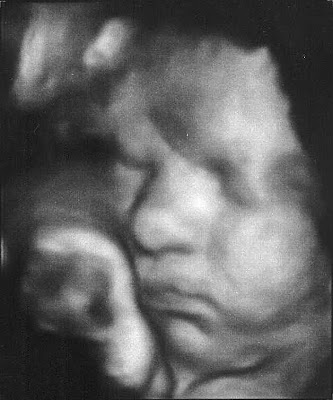

So 35 weeks. That was the goal they set for me. I made it. I went to high risk doctor today and got to see what Trouble looks like again. They are putting his weight now at 5lbs6oz.

He's got his Momma's cheeks :o)

Gotta little Elvis lip going on here I think

Look at how that arm is bent. That's got to be uncomfortable. Actually, now that I look at them all....In the first picture I posted, it looks like he has it bent under him like a little pillow.